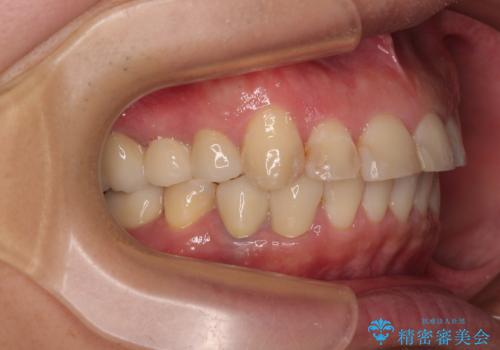

矯正治療にやや時間がかかりましたが、歯列はきれいに整い、気になっていたむし歯や銀歯は自然な色合いに仕上がりました。